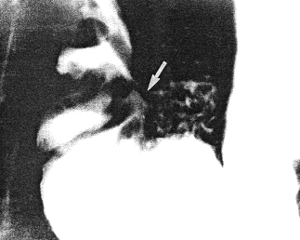

She then presented with a recurrence of symptoms. Endoscopy showed pyloric deformity. Radiographic examination three weeks later revealed an ulcer on the lesser curvature of the pyloric sphincteric cylinder, on the immediate oral side of the ring, with a fistulous communication between the ulcer and the superior fornix of the duodenal bulb (Fig. 31.3). Prominent, permanent circular mucosal folds were present in the cylinder, which remained partially expanded throughout the examination with complete absence of cyclical contraction and relaxation. Repeat endoscopy the following week confirmed the presence of a prepyloric ulcer with a pyloro-duodenal fistula.

![]() |

| Fig. 31.3. Case S.D. Ulcer lesser curvature side of sphincteric cylinder with fistula (arrow) to base of duodenal bulb. Partial expansion of cylinder. Permanent, circular mucosal folds in cylinder |